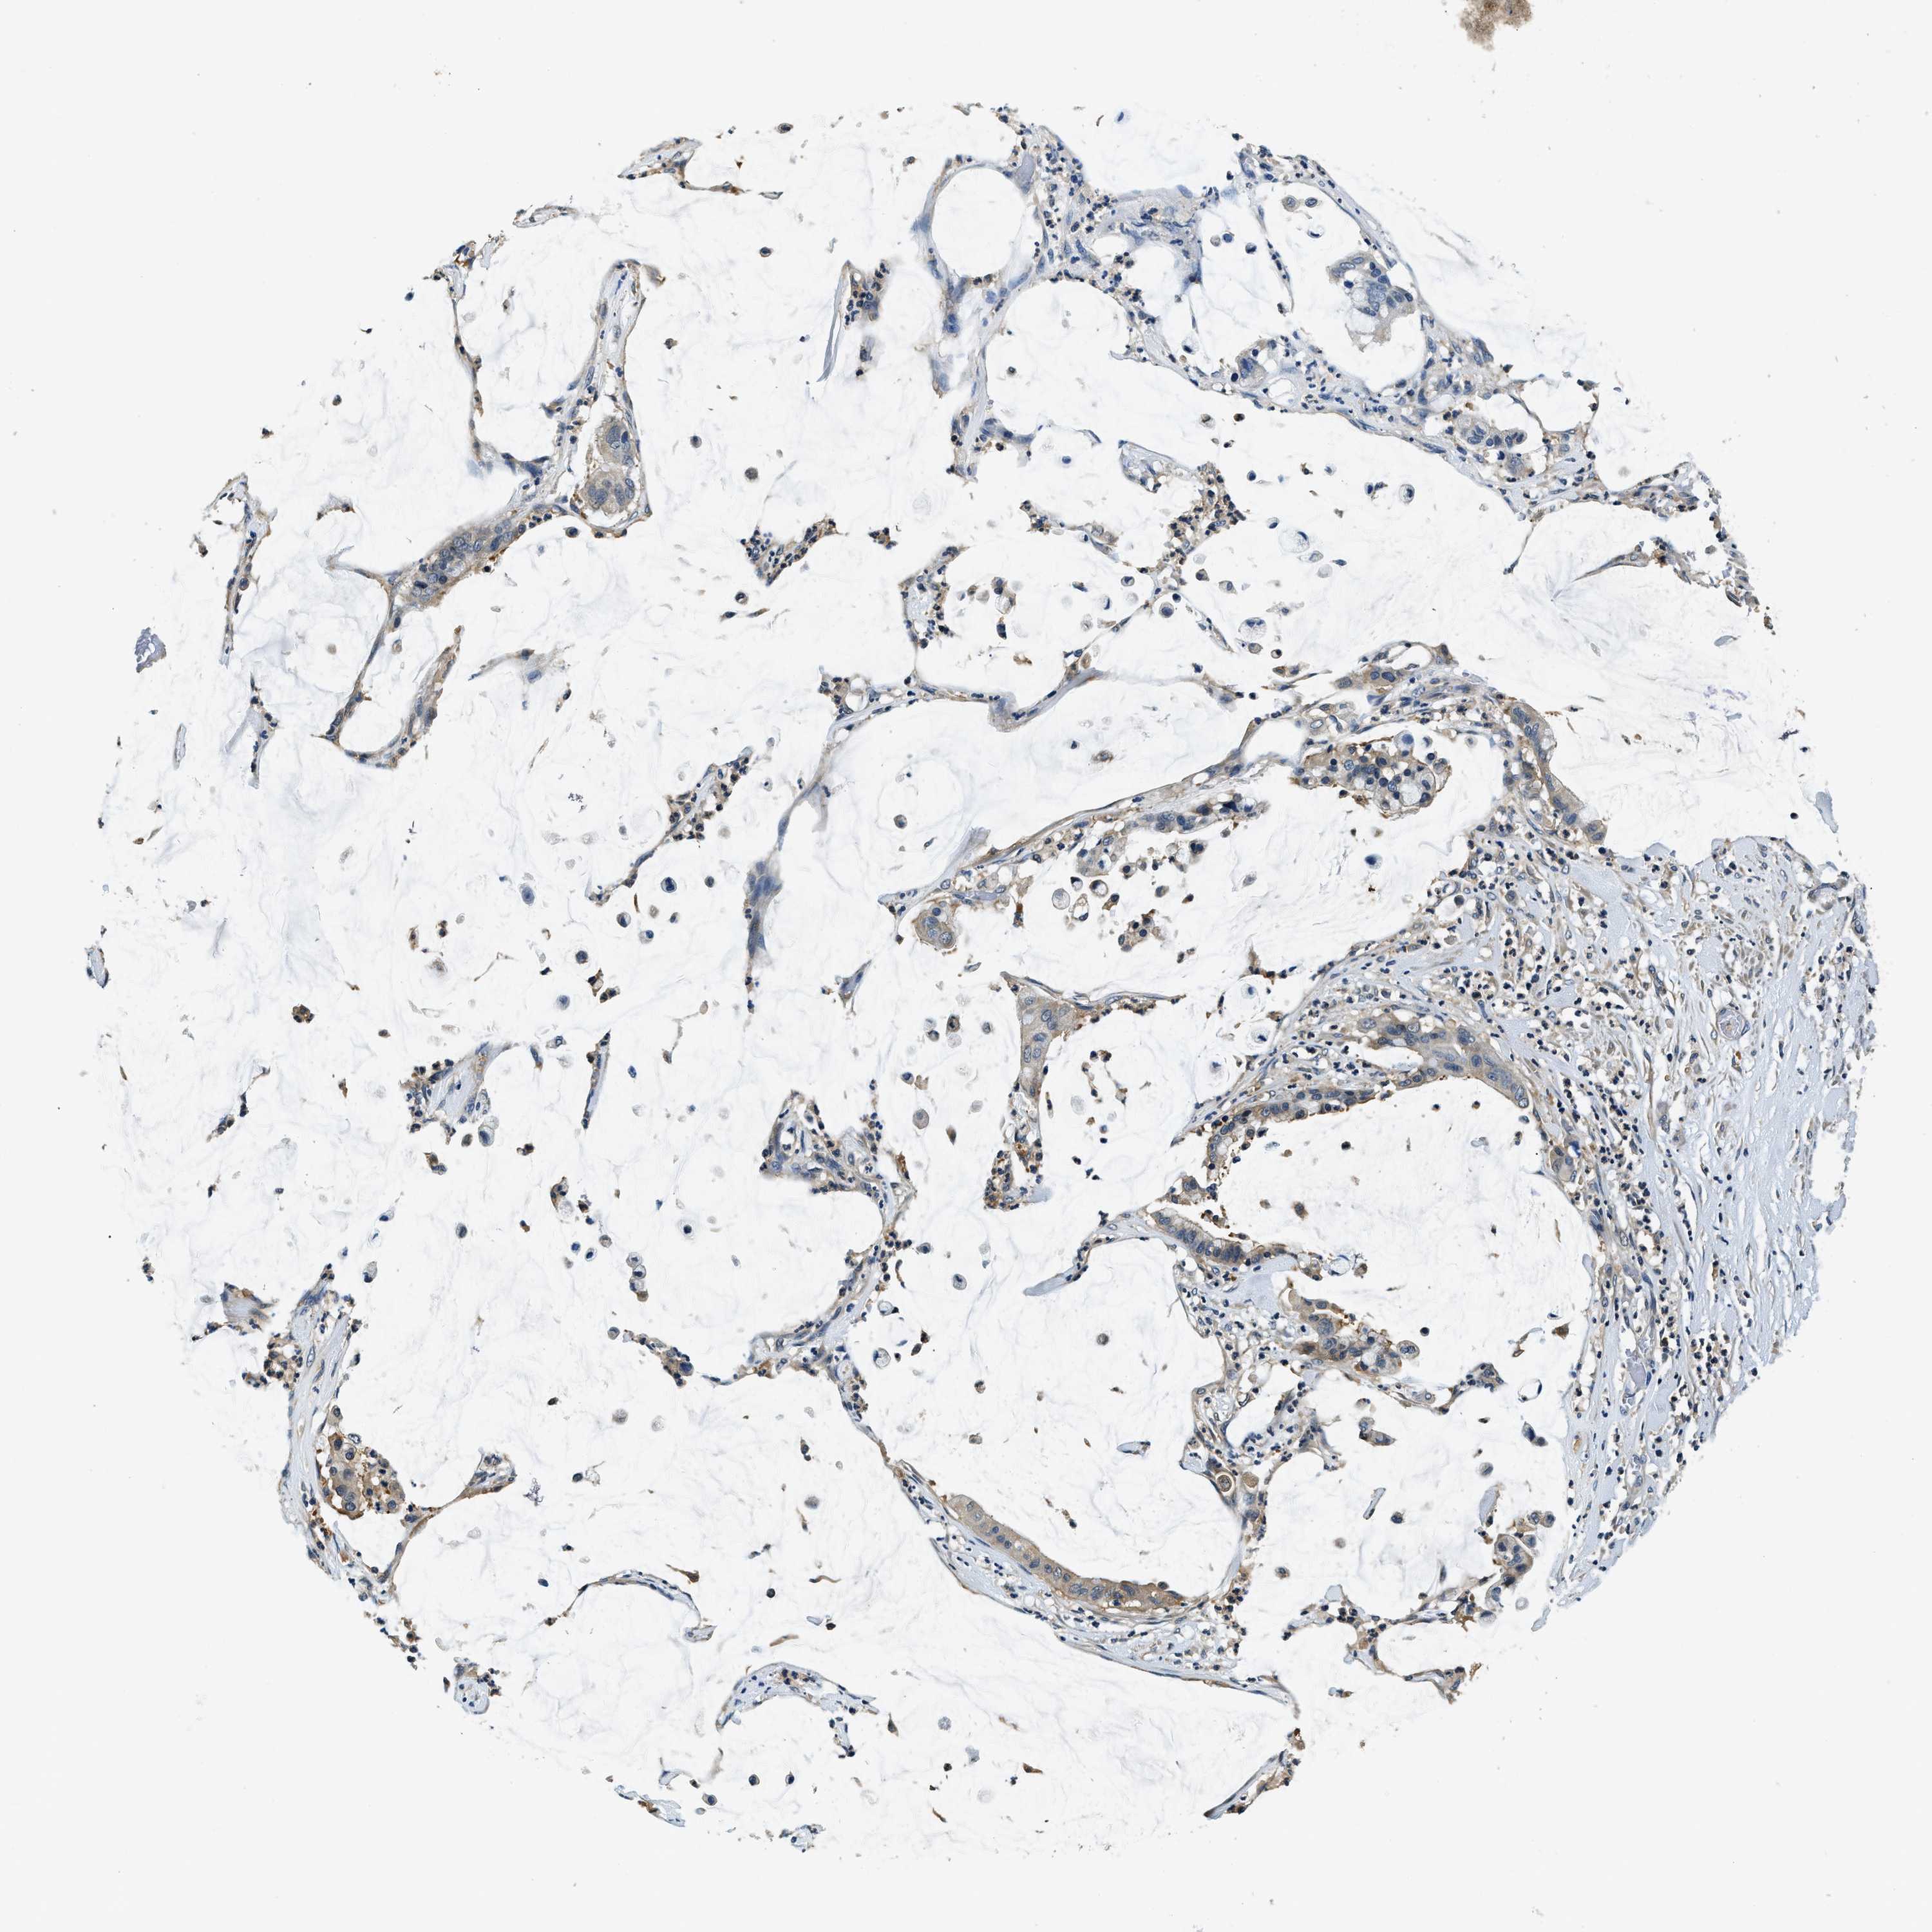

PANCREATIC CANCER - Protein expressioni

A mouse-over function shows sample information and annotation data. Click on an image to view it in a full screen mode. Samples can be filtered based on level of antibody staining by selecting one or several of the following categories: high, medium, low and not detected. The assay and annotation is described here.

Note that samples used for immunohistochemistry by the Human Protein Atlas do not correspond to samples in the TCGA dataset.

Antibody stainingi

Antibody staining in the annotated cell types in the current human tissue is reported as not detected, low, medium, or high, based on conventional immunohistochemistry profiling in selected tissues. This score is based on the combination of the staining intensity and fraction of stained cells.

Each image is clickable and will lead to virtual microscopy that enables deeper exploration of all samples and also displays staining intensity scores, fraction scores and subcellular localization as well as patient and tissue information for each sample.

Antibody HPA013816

Antibody HPA015622

Staining

High

Medium

Low

Not detected

Intensity

Strong

Moderate

Weak

Negative

Quantity

>75%

75%-25%

<25%

None

Location

Nuclear

Cytoplasmic/membranous

Cytoplasmic/membranous,nuclear

Adenocarcinoma, NOS